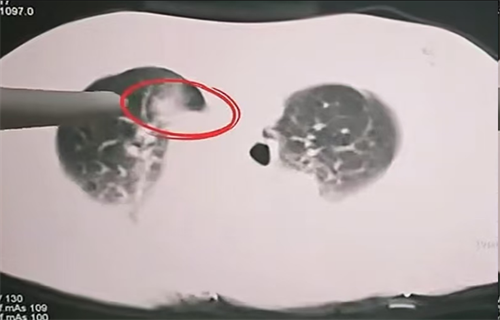

消融范围完美覆盖肺部病灶